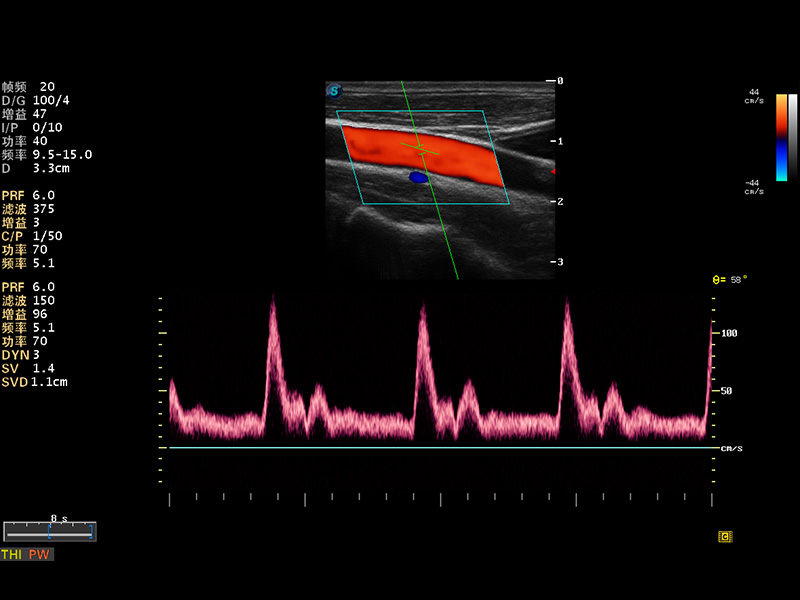

S8 EXP便携式彩色多普勒超声诊断仪是银河集团官网研发的高端全身应用型便携彩超。高通道的VIS平台融合可视化(Visual)、智能化(Intelligent)和人性化(Smart)的特点,配以银河集团官网自主研发生产的探头大家族,使您能够快速、准确的获得病人信息,提高工作效率的同时减轻疲劳。

成像技术

多波束形成器

μ-Scan微米成像

谐波成像

实时宽景成像

空间复合成像

3D/4D成像